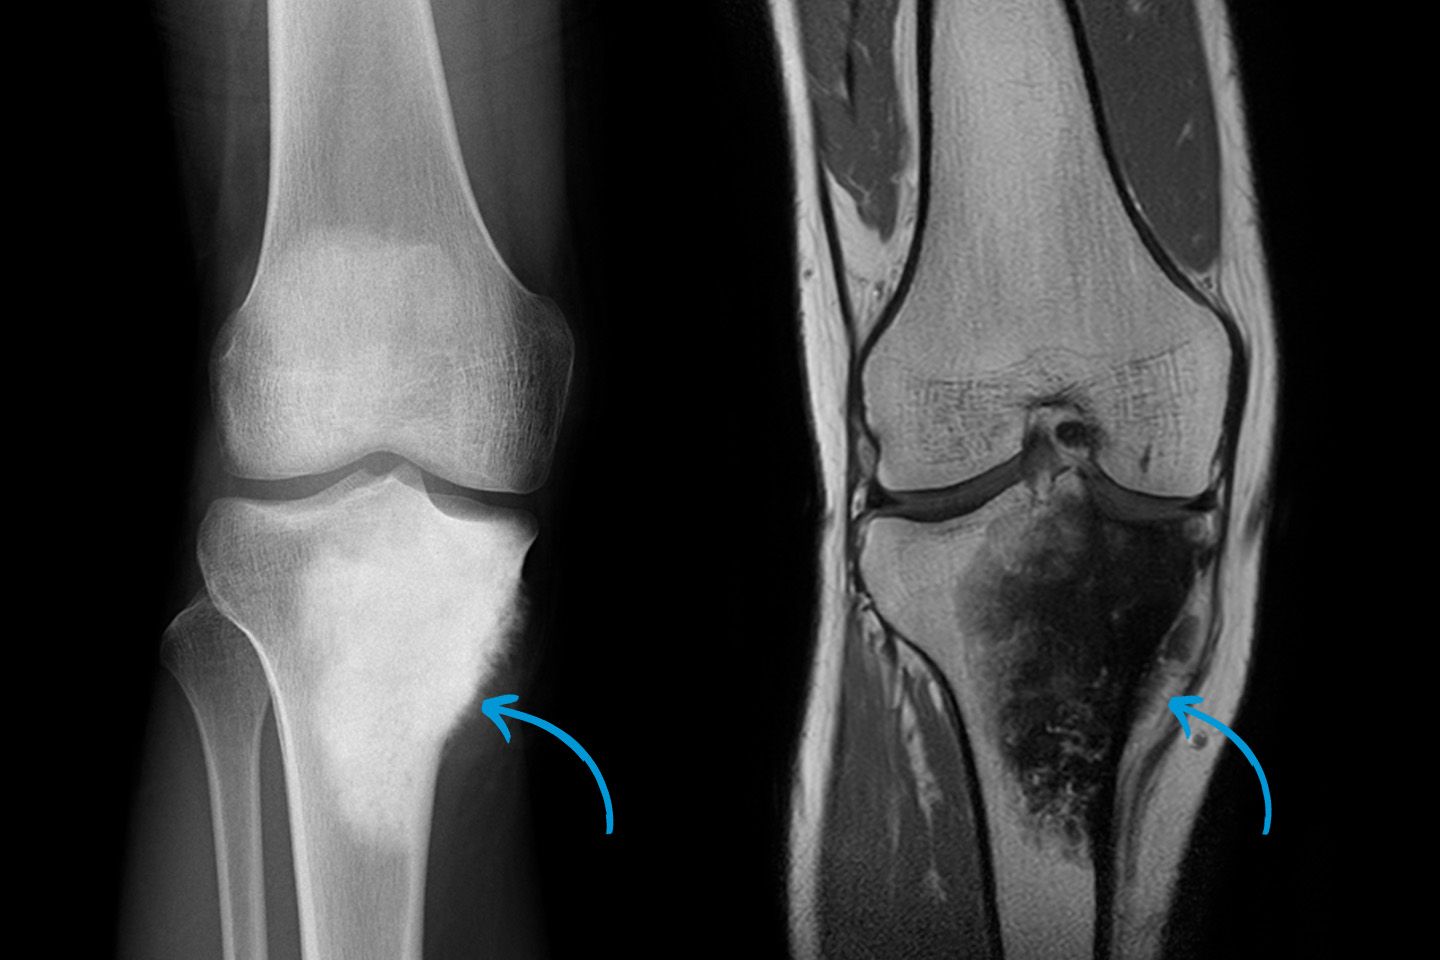

Osteosarkom (bösartiger Tumor des Knochens) am Kniegelenk.

Durch den Einsatz moderner Verfahren wie Ultraschall, Röntgen, Magnetresonanztomographie (MRT) und Computertomographie (CT) können wir präzise Bilder des Bewegungsapparates erstellen. Diese ermöglichen es, die Ursachen von Beschwerden zu erkennen und gezielte Behandlungen einzuleiten. Dazu zählen Frakturen, Bänderverletzungen, Gelenkerkrankungen, degenerative Erkrankungen oder Tumorerkrankungen. Moderne Datenverarbeitung, wie die Integration von 3D-Bildgebung und hochauflösenden Techniken, gewährleistet präzise Diagnosen auf höchstem Niveau.